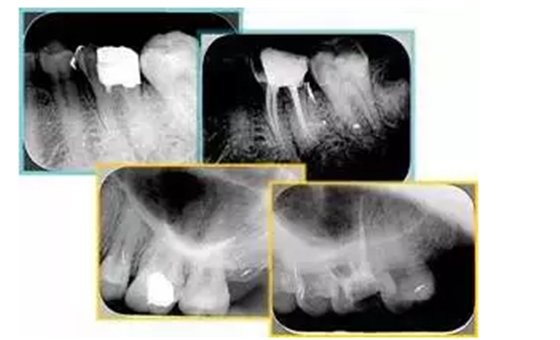

共有 4 張 X 線片,分別是術(shù)前、診斷絲 、主牙膠尖確認(rèn)、術(shù)后。

( 1 )術(shù)前:術(shù)前 X 線片用來了解牙齒的大概情況。術(shù)前預(yù)期為多根牙時(shí) X 線片應(yīng)偏頭拍攝。

( 2 )診斷絲:根據(jù)術(shù)前 X 線片進(jìn)行開髓、根管的初步預(yù)備后,需要插入診斷絲,用來指示工作器械位置。常用 10 號或 15 號擴(kuò)大器作為診斷絲插入牙髓腔。

( 3 )主牙膠尖確認(rèn):通過術(shù)前預(yù)期和診斷絲診斷,明確工作長度、牙根走向,進(jìn)行根管預(yù)備。之后應(yīng)進(jìn)行主牙膠尖(中銼)確認(rèn),已明確根管是否適合充填。

( 4 )術(shù)后:觀察治療效果。

左圖為根管充填術(shù)后 X 線片。圖中可見,根管充填較好。右下圖有白色小點(diǎn),為側(cè)方加壓導(dǎo)致糊劑擠出所致,表明根管充填比較致密。